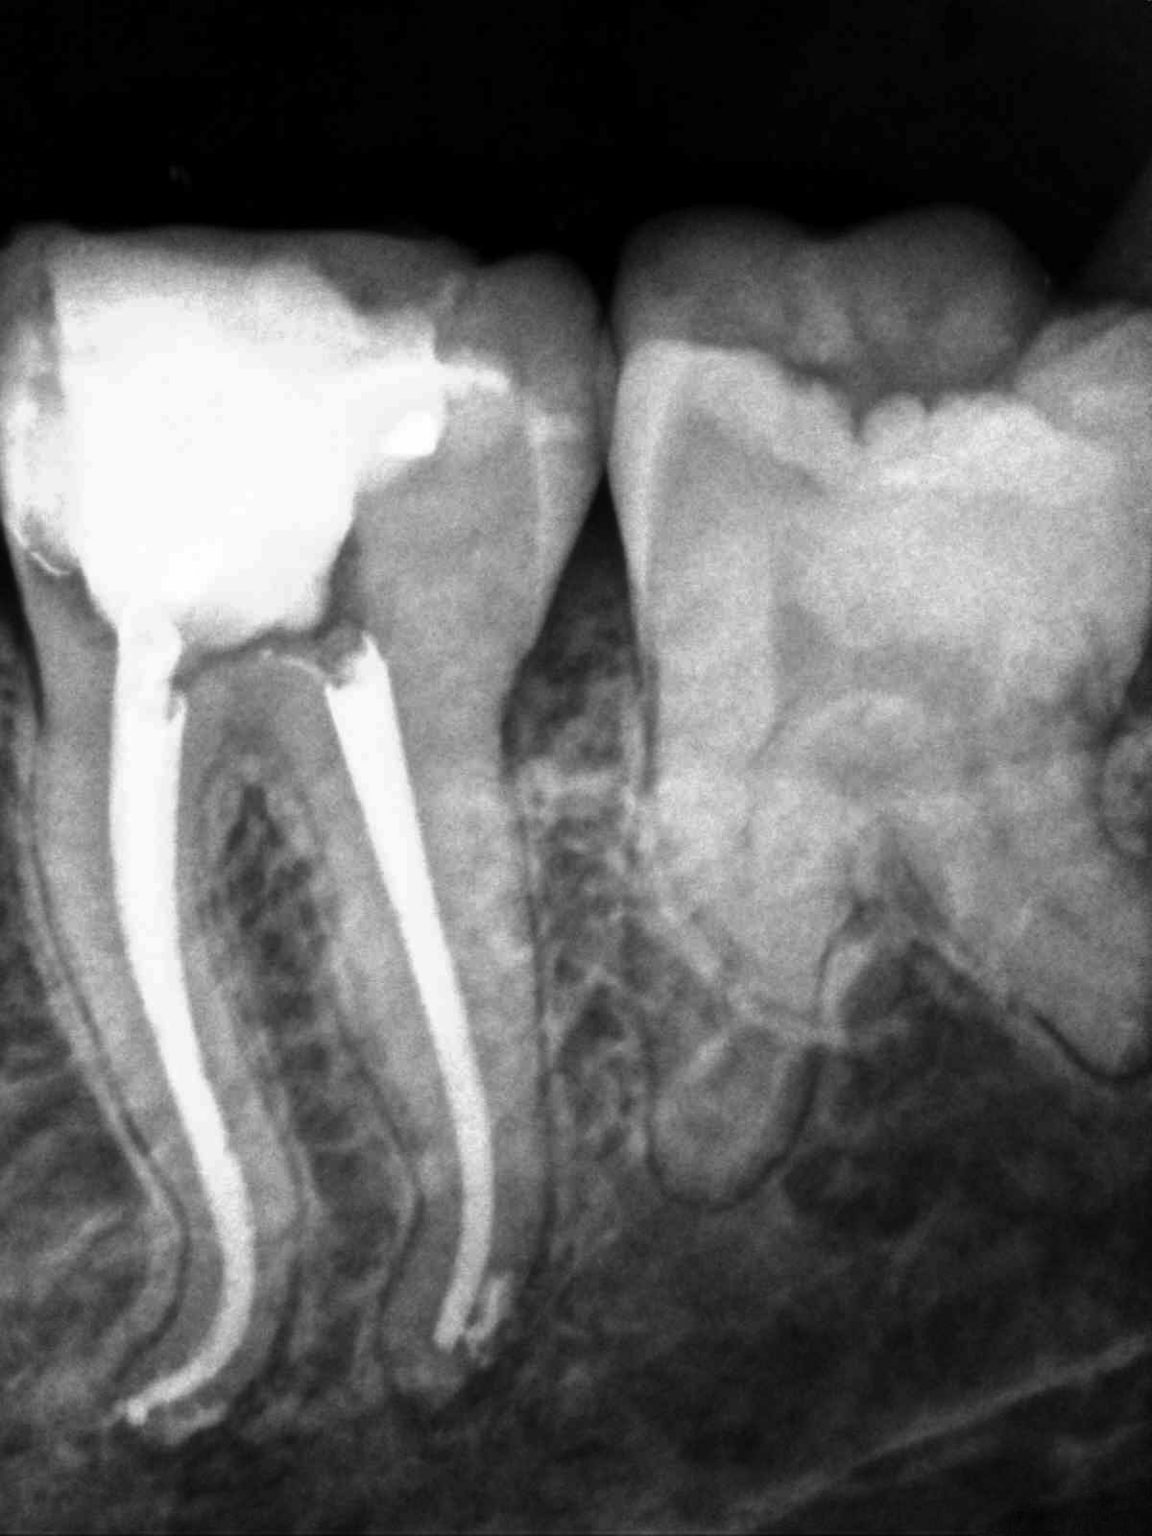

Conventional endodontic therapy of a mandibular second molar with Describe Diagnostic Conclusions For Endodontic Therapy • describe diagnostic conclusions for endodontic therapy. Describe the types of endodontic procedures. • discuss the medicaments and dental. The guide to clinical endodontics outlines the current best practices in endodontic diagnosis and treatment. Give the types of diagnostic conclusions for endodontic therapy. • list the types of endodontic procedures. Sbu has evaluated the methods used by dentists to diagnose,. Describe Diagnostic Conclusions For Endodontic Therapy.